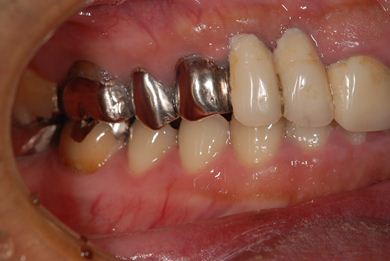

| 性別/年齢 | 男性 / 46歳 | ||||||||||||||||||||||||||||||||

| 治療内容 | インプラント2本(抜歯即日スピードインプラント)、ハイブリッドセラミック2本 | ||||||||||||||||||||||||||||||||

| 総治療費 | 456,750円 | ||||||||||||||||||||||||||||||||

| 治療期間 | 7ヶ月 |